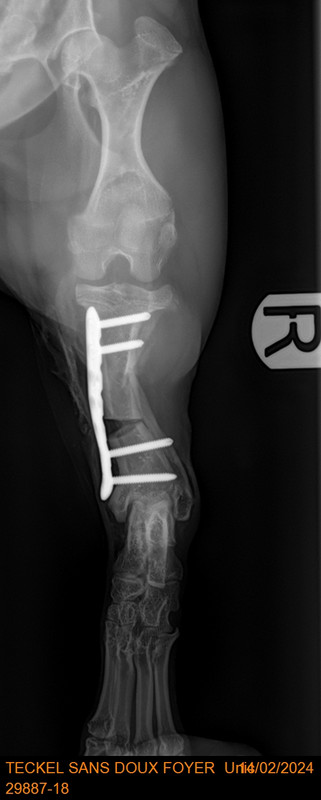

voici les radios avec les plaques qui ont été mises pour redresser

[Image: 29887-18-TECKEL-SANS-DOUX-FOYER-Unic-13382.jpg]

impressionnant !

C est impressionnant..il va se sentir mieux pour marcher [Image: coeur%20joyeux.gif] [Image: coeur%20joyeux.gif] [Image: calin-1844.gif] [Image: calin-1844.gif] [Image: des%20bisous.gif] [Image: des%20bisous.gif]